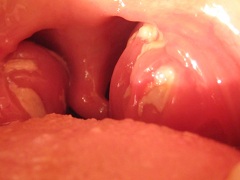

Поражение ротоглотки – постоянный симптом инфекционного мононуклеозаПоражение ротоглотки – постоянный симптом инфекционного мононуклеоза. У больных наблюдается отечность и увеличение небных миндалин, поражение носоглоточной миндалины, что, в свою очередь, обуславливает затруднение носового дыхания, выраженную заложенность носа, сдавленность голоса, «храпящее» дыхание ртом. Для инфекционного мононуклеоза характерен задний ринит, поэтому выделения из носа обычно не наблюдаются в период обострения болезни, они появляются лишь после восстановления носового дыхания. У больных отмечается отечность задней стенки глотки, которая обычно покрыта густой слизью. Во время болезни наблюдается умеренная гиперемия зева и незначительная боль в горле.

Инфекционный мононуклеоз у детей в 85% случаев сопровождается налетом на носоглоточных и небных миндалинах. Как правило, появление данного симптома (в самом начале или на 3-4 день болезни) вызывает еще большее повышение температуры и ухудшение общего состояния.